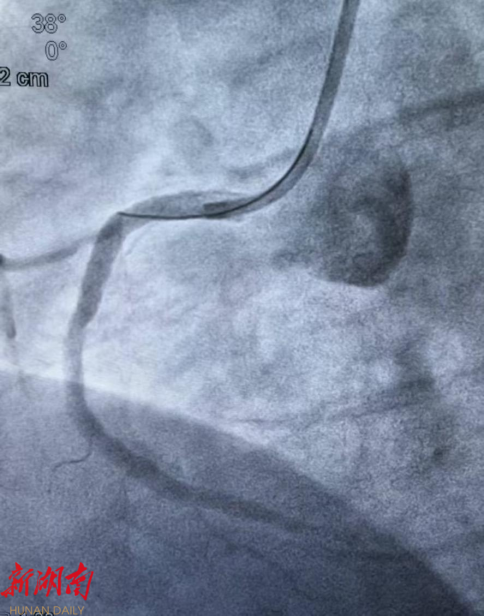

复查心电图明确诊断为急性下壁心肌梗死,病情极其凶险。冠脉造影结果显示:冠脉三支严重病变,其中右冠状动脉中段急性完全闭塞,伴大量血栓影,合并右冠自发性夹层,属于极高危复杂病变,随时可能再次发生恶性心律失常 、 心源性休克甚至猝死。

(术前冠脉造影)